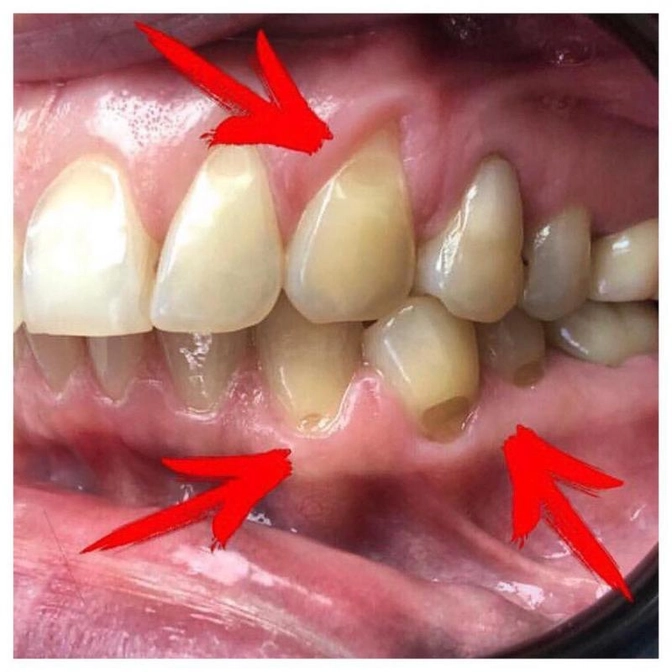

Стрелками на фото как раз это показано - называется "абфракционный дефект зубов".

Наиболее тонкая, а значит и уязвимая, эмаль - в пришеечной области зуба.

При таких дефектах пациент ощущает чувствительность, боль при чистке зубов, приеме холодной, горячей или кислой пищи, а может и вовсе не предъявлять жалоб.